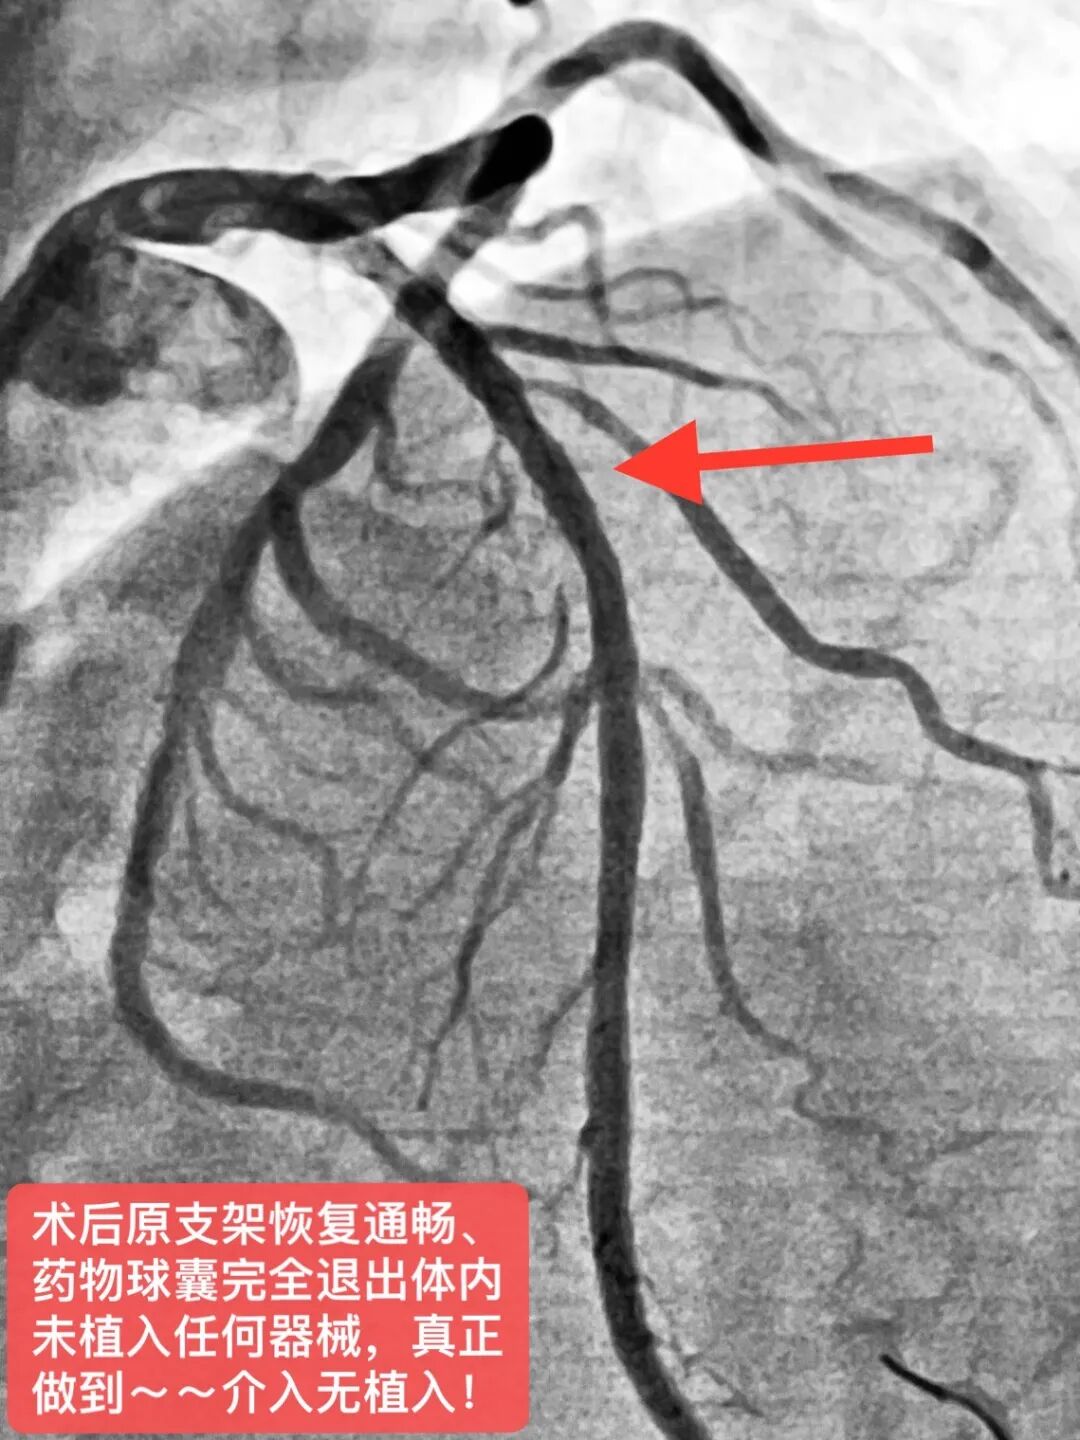

导读 心脏介入无植入,“药物球囊”显奇效!近日,县域首例支架内再狭窄药物球囊扩张术在玉山中医院顺利完成。 患者汪老伯,8年前因急性心梗在外院于前降支植入一枚支架,近一年反复出现胸闷、胸痛不适症状来县中医院就诊。经评估后考虑支架再狭窄可能,复查冠脉造影提示原支架内重度再狭窄。如在原支架内狭窄处叠加支架可能会明显增加再次狭窄风险,并且对血管弹性有明显影响,药物球囊扩张术是所有指南的优先推荐。经心脏介入科徐承权手术团队充分讨论并告知患者家属病情后,决定采用DCB(药物球囊)技术处理。术后患者症状即刻改善,立竿见影,3天后康复出院。

药物球囊的外表涂有一层可以抑制血管内皮增生的药物,医生通过患者手腕处的微小创口送入导管和药物球囊,用30至60秒的时间扩张球囊,把药物直接释放至冠状动脉的病变部位,在解除狭窄的基础上同时达到抑制血管内皮增生作用,保证血管通畅,降低再狭窄和血栓发生风险。 药物球囊与支架最大的不同在于没有任何金属植入物残留于患者体内,但是药物作用时间可以持续到手术以后的数月之久,这就解决了由于内皮增生导致的介入术后血管再狭窄的问题,为不适合支架植入的患者带来了福音。 药物球囊目前适用于: 1、支架内再狭窄,避免在支架内植入支架;2、小血管病变不宜植入支架者;3、有高出血风险患者,或需要缩短双联抗血小板治疗时间;4、分叉病变不宜植入支架患者;5、拒绝体内异物的患者。但也有临床研究认为,对于普通冠心病患者,也可考虑单纯药物球囊扩张,特别是糖尿病患者、年轻患者及高出血风险患者,因为糖尿病患者有较高的支架内再狭窄的比例;年轻患者由于年龄原因,对支架植入顾虑较多,甚至有抵触情绪;而高出血风险患者植入药物球囊后很短时间双抗后即可改为单抗治疗,避免了长期吃双抗带来的脑出血、胃肠道出血等致命风险。但药物球囊缺乏金属骨架因而不能预防急性弹性回缩的发生,亦不可用于处理血管夹层病变。 目前的临床随机对照试验已显示,在良好病变预处理基础上,结合功能学检测,DCB可有效抑制内膜增生,并有DAPT时间较短的优势,已成为许多临床情况下治疗冠脉病变的有效选择。DCB用于ISR治疗已是标准方案并得到指南推荐,不仅如此,DCB治疗冠脉新生小血管病变也被认为是DES的有效替代方案。此外,越来越多的证据表明,其它冠脉病变如分叉病变、大血管病变,甚至更复杂冠脉病变的介入治疗,都可能从单纯DCB治疗策略中获益。